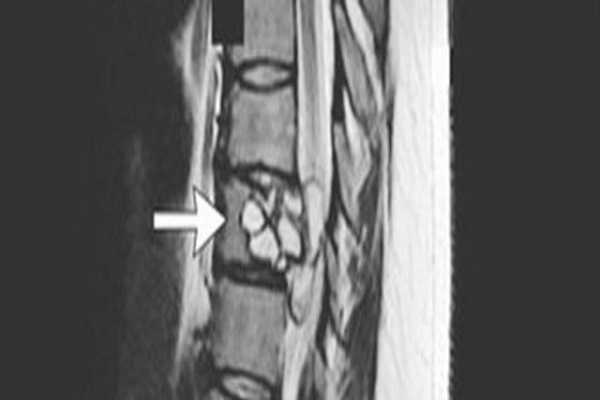

La donna, infatti, era tre mesi che avevaanche difficoltà a camminare. Nei fatti la trentacinquenne francese cadeva spesso e non sentiva più le gambe. Il loro funzionamento era deficitario e la sensibilità che aveva negli arti inferiori era notevolmente ridotto. I medici della struttura sanitaria a cui la donna si era rivolta, l'hanno sottoposta ad una risonanza magnetica, per capire i motivi dei suoi disturbi. Da questo esame è emerso che nella schiena la signora aveva una tenia di cane. La cosa strana è che mai la donna era stata a contatto con dei cani. Resta quindi un mistero come il parassita sia entrato all'interno del suo corpo.Rimozione del parassita

Nella rivista New England Journal of Medicine, è stato spiegato il procedimento di rimozione del parassita, una tenia di cane, dalla spina dorsale, che è avvenuto attraverso l’utilizzo di una siringa per l'epidurale. L'intervento è stato necessario, non solo per debellare l'origine dei disturbi di cui era affetta la donna, ma anche perché, la tenia di cane può causare un'infezione che può portare a lesioni cistiche nel fegato e nei polmoni, nel sistema nervoso centrale e nelle ossa. La donna, oltre all'intervento è stata anche sottoposta ad una terapia antiparassitaria e ora sembra stare molto meglio.Articolo Precedente